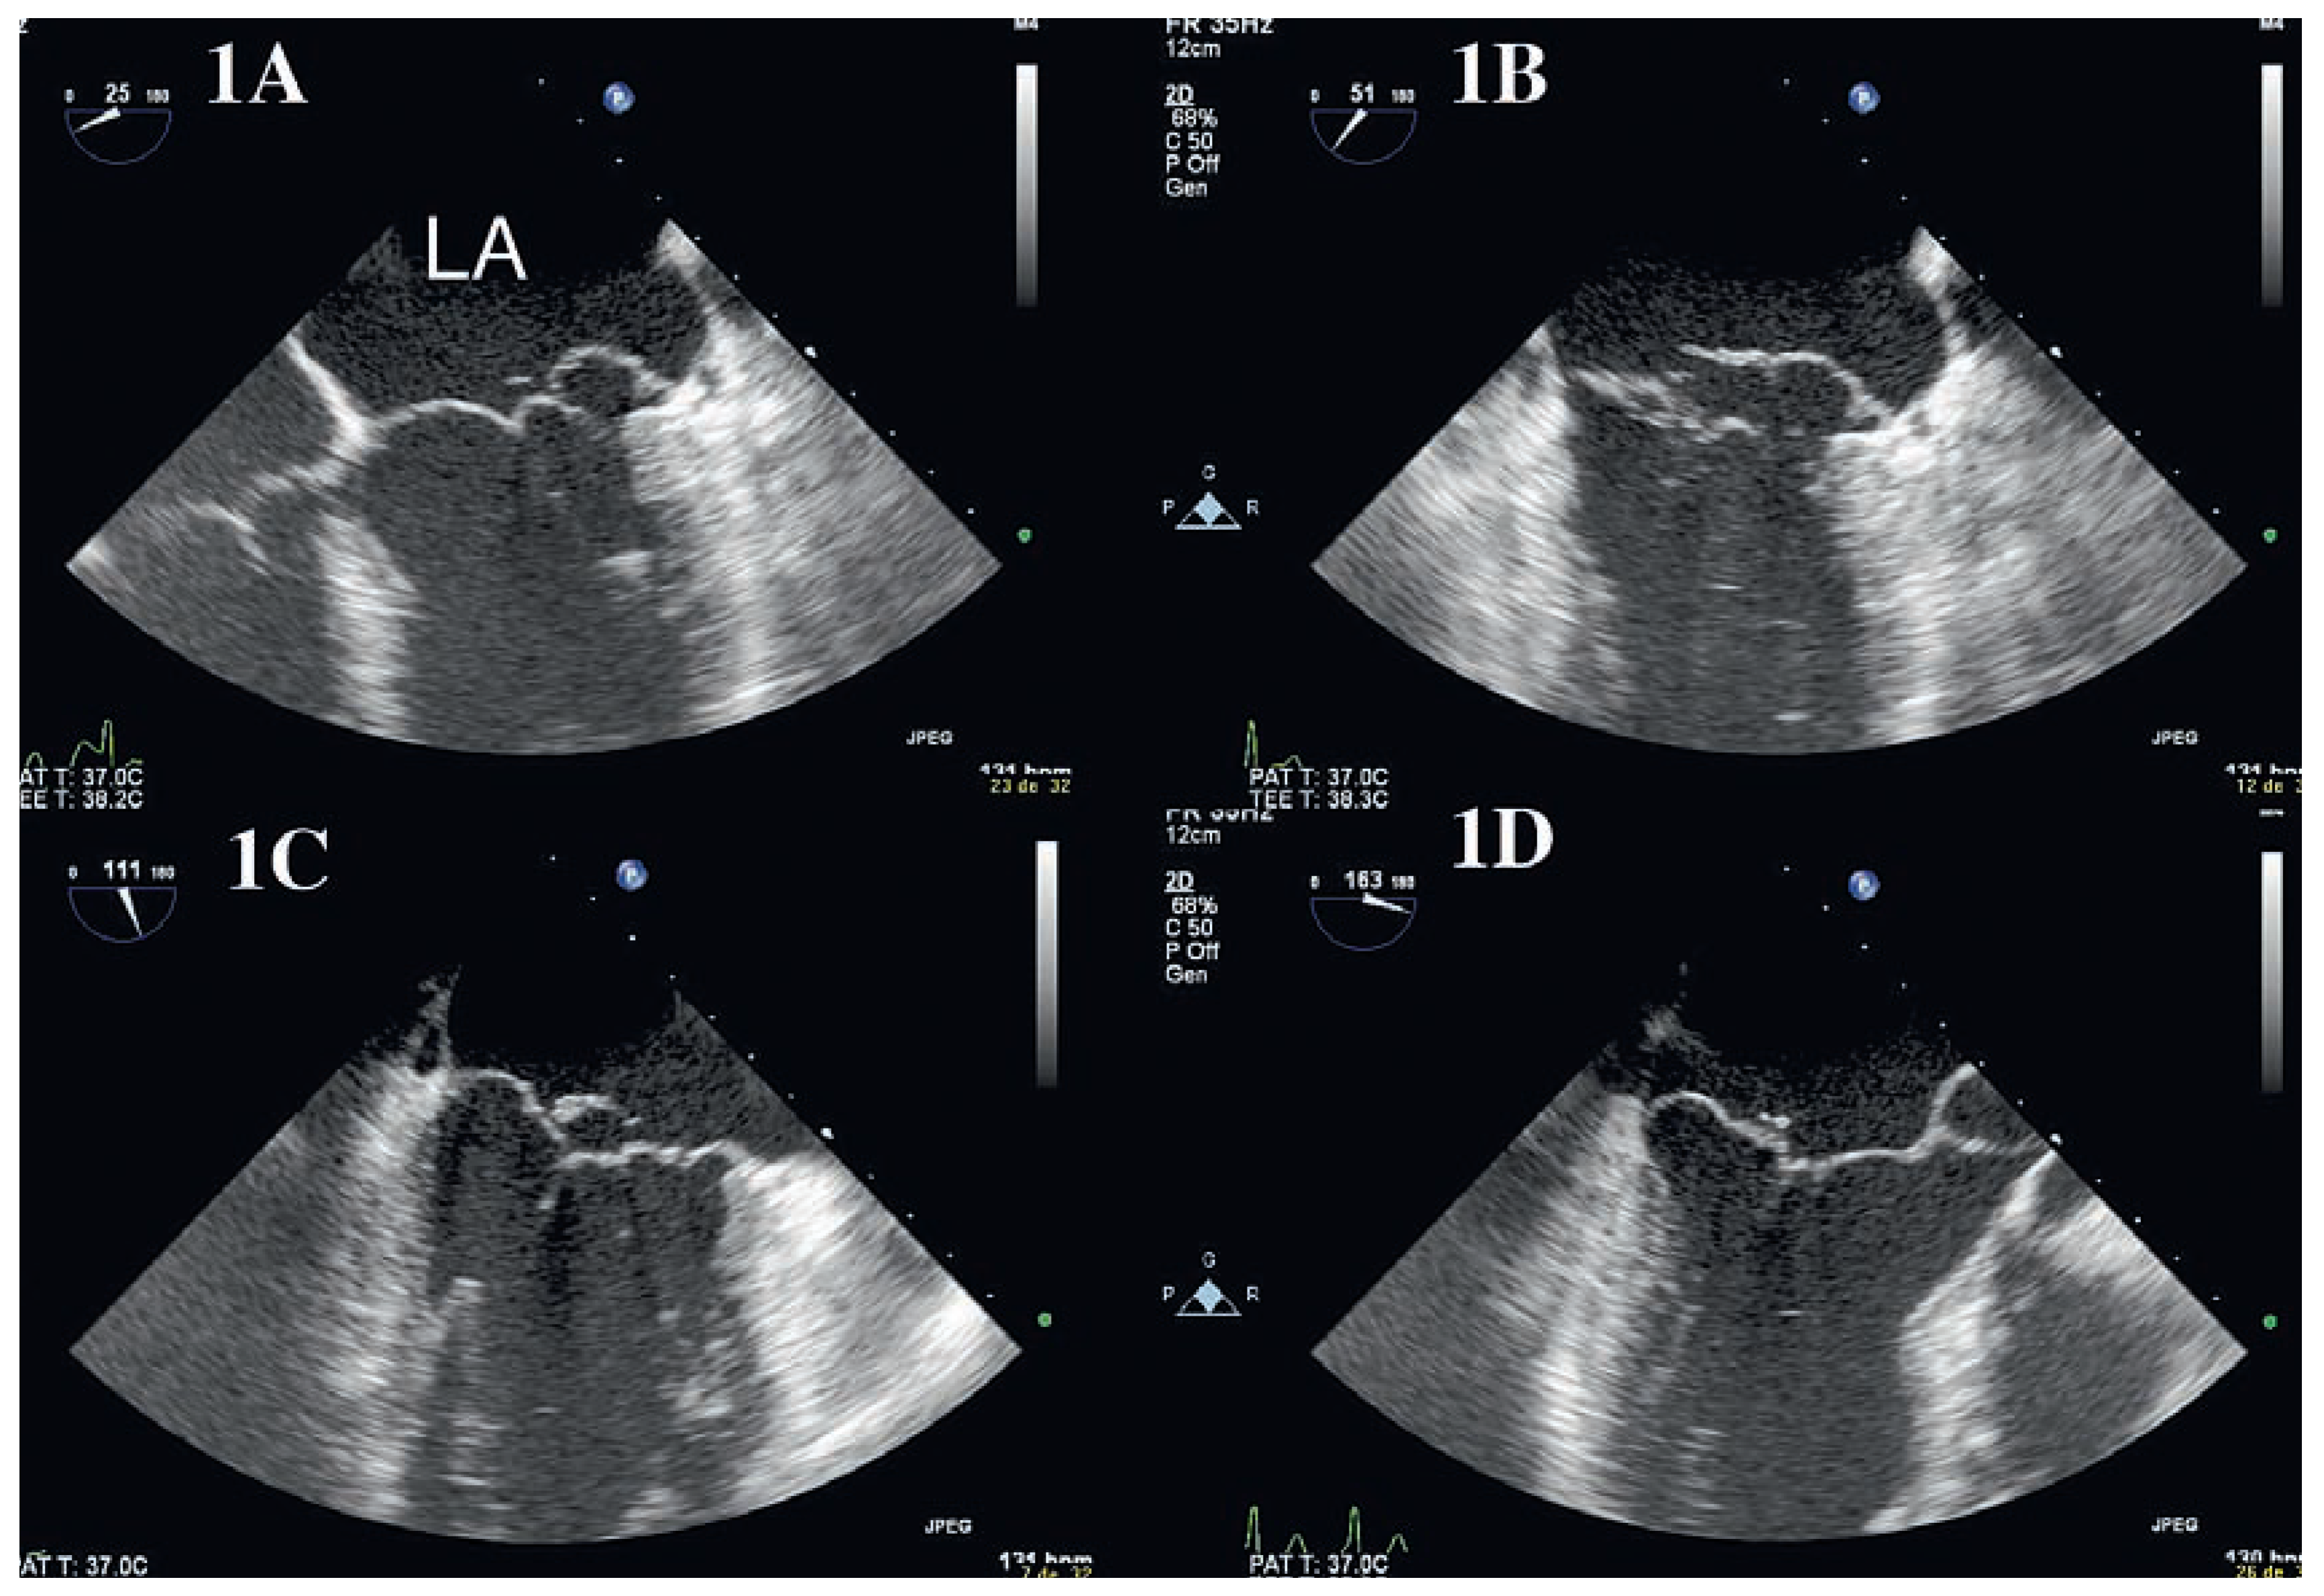

Insuffisance Mitrale: Apport de L’échographie Tridimensionnelle

Case report